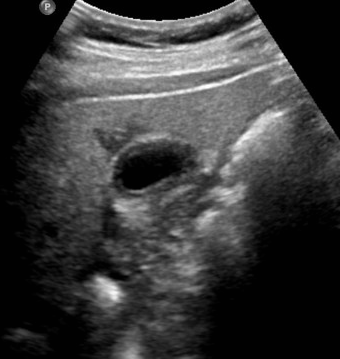

Identify this image.

Early stage echinococcal or Hydatid cyst